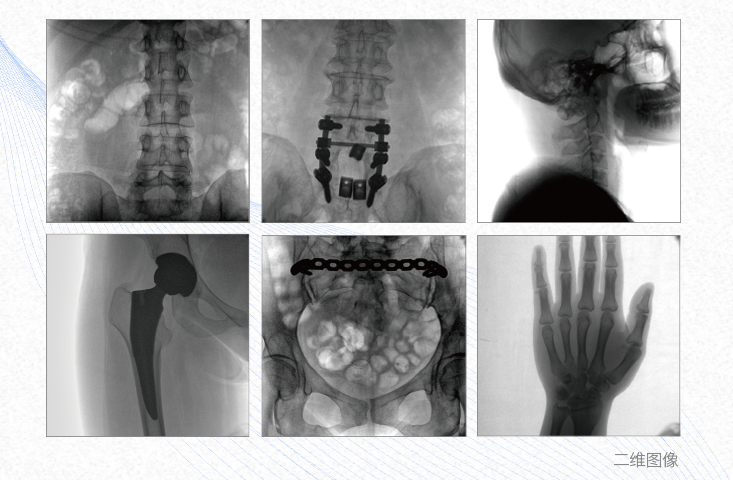

一、平板3DC形臂臨床應(yīng)用廣泛

1、脊柱外科

有效重建復(fù)雜的脊柱三維模型,提供準(zhǔn)確的二維、三維圖像,提高螺釘植入的準(zhǔn)確性,縮短手術(shù)時(shí)間,減少并發(fā)癥的概率,降低輻射的攝入。

2、創(chuàng)傷外科

例如骨盆骨折內(nèi)固定術(shù),可術(shù)中三維重建髖臼關(guān)節(jié)面,準(zhǔn)確定位并植入螺釘,有效縮短螺釘植入的時(shí)間和透視暴露時(shí)間,減少術(shù)中及術(shù)后并發(fā)癥發(fā)生的概率。

3、關(guān)節(jié)外科

主要應(yīng)用于肩關(guān)節(jié)、肘關(guān)節(jié)、髖關(guān)節(jié)、膝關(guān)節(jié)的關(guān)節(jié)置換及解剖復(fù)位的定位。它可以準(zhǔn)確地置入假體,減少輻射時(shí)間,降低輻射劑量。

4、截骨矯形外科

例如治療先天性脊柱側(cè)后凸畸形,可有效引導(dǎo)術(shù)者植入后路螺釘并切除半錐體,達(dá)到滿意的截骨矯正效果。